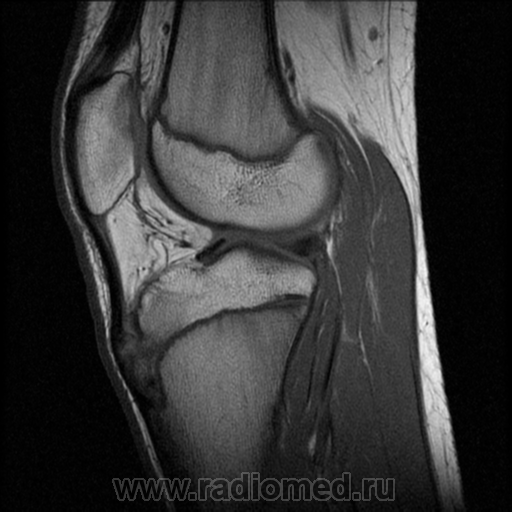

А вот так данная патология выглядит на МРТ:

Добрый админ: "А вот так данная патология выглядит на МРТ".

Представленный Вами случай, с Вашего позволения, будет "забран" в набор изображений - "остеохондропатии".